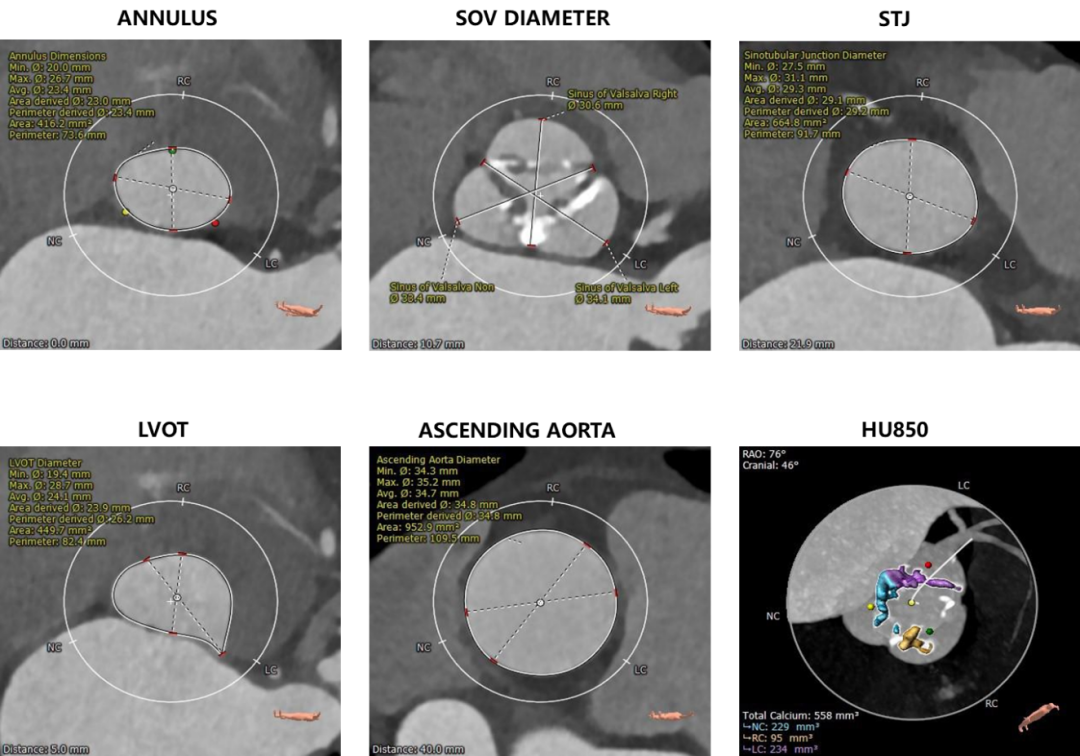

术前CT评估

三叶式主动脉瓣,重度钙化,钙化主要分布在瓣叶边缘及附着缘,分布不均,左无窦钙化重,右窦钙化相对较轻,瓣叶明显增厚,左无窦交界钙化性粘连,

冠脉开口高度可,左冠瓣瓣叶长度>冠脉开口到瓣叶附着缘距离;冠脉散在钙化,

瓦氏窦内径尚可,窦管交界、升主动脉内径可,

瓣环平面与水平面夹角44°,非横位心,主动脉弓宽度及角度尚可。流出道呈敞口型,左室心腔内径尚可,

主动脉根部测量

瓣环上测量